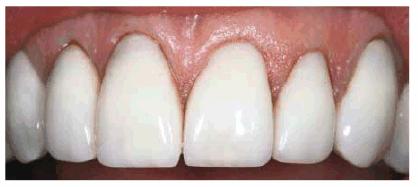

chromogenic foods, and beverages (Figures 16-16A 16-16B 16-17A, and 16-17B). Although these types of stains

generally require only 2 to 6 weeks of bleaching treatment, some are more

stubborn. Nicotine staining of long-term duration may require as long as 3

months of nightly treatment (Figures 16-18A, and 16-18B).48 Tetracycline

Figure 16-16A: Some teeth darken over time from chromagenic foods. Some patients' teeth are just naturally yellow.

Figure 16-16B: Whitening of the maxillary teeth using 10% carbamide peroxide in a custom tray results in a more pleasing smile. This patient is now interested in closing the spaces.

Figure 16-17A: Some teeth darken through natural aging.

Figure 16-17B: Whitening of the maxillary teeth using 10% carbamide peroxide in a custom tray produces a normal progression of color from gingival to incisal edge but offers a more pleasing, younger look to the patient.